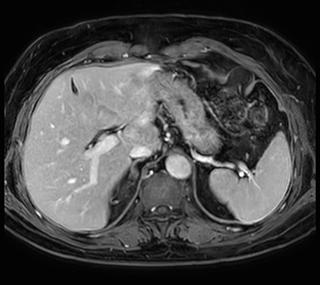

Free breathing abdominal MRI with VitalEye

Ascites can be hard to image, but excellent result is obtained with Ingenia Ambition. This high resolution image demonstrates the high quality that can be obtained with VitalEye and the patient just breathing normally. The acquisition time is fast thanks to the accuracy of the respiratory gating with VitalEye** and it also saves the time needed to put a respiratory belt on the patient.

3D T2 with VitalEye

3D T2 with VitalEye